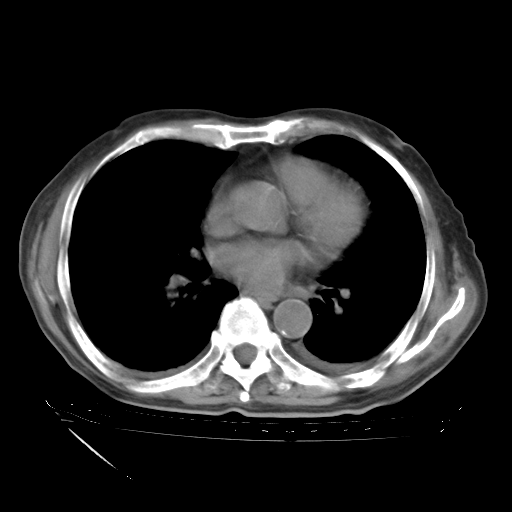

甲强龙80mg/日+抗结核治疗(异烟肼+利福霉素+乙胺丁醇)10天。复查肺部CT。

治疗10天肺部CT

补充下:5月9日胸部CT:似乎已见双下肺胸腔积液了,鉴于目前有下肢水肿,肝功示:白蛋白低,应注意多浆膜腔积液(漏出液可能大?),需注意!